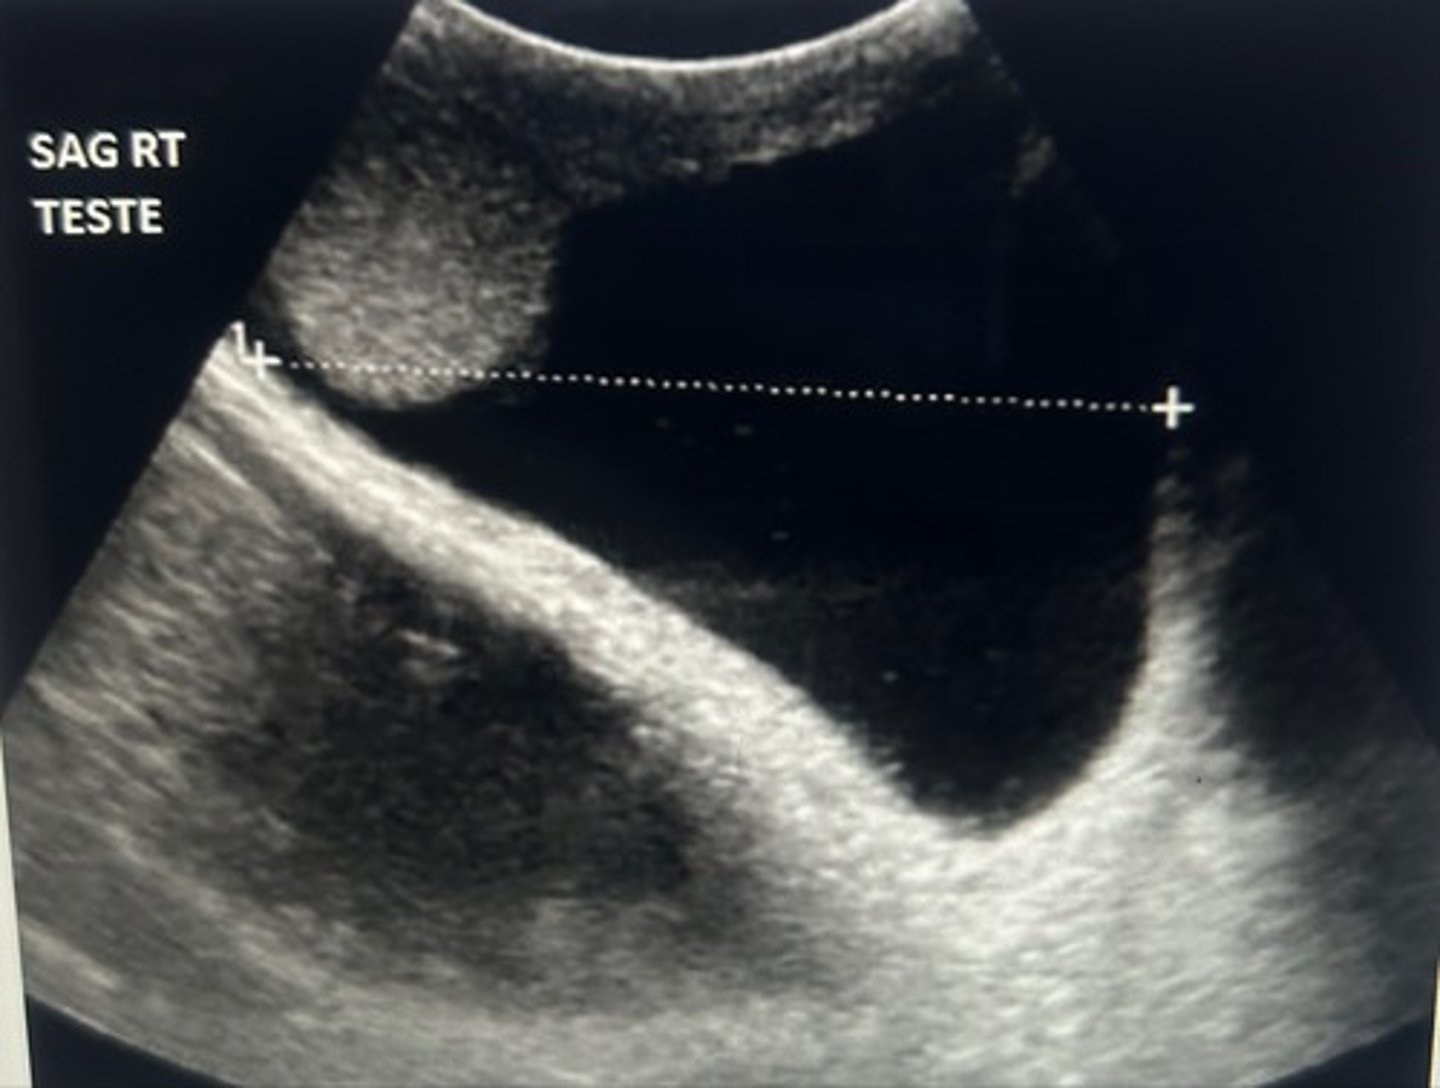

The following images of taint on a 12-year-old boy with a non-palpable, right testicle. What should be your next step as a sonographer performing this exam?

Evaluate the right groin for an on the undescended testicle

The testicles form in the lower pelvic region and migrate to the scrotal sac after 36 weeks of gestational age. When the scrotal sac is found to contain only one testicle, the undescended testes is most commonly found along the inguinal canal of the affected side.